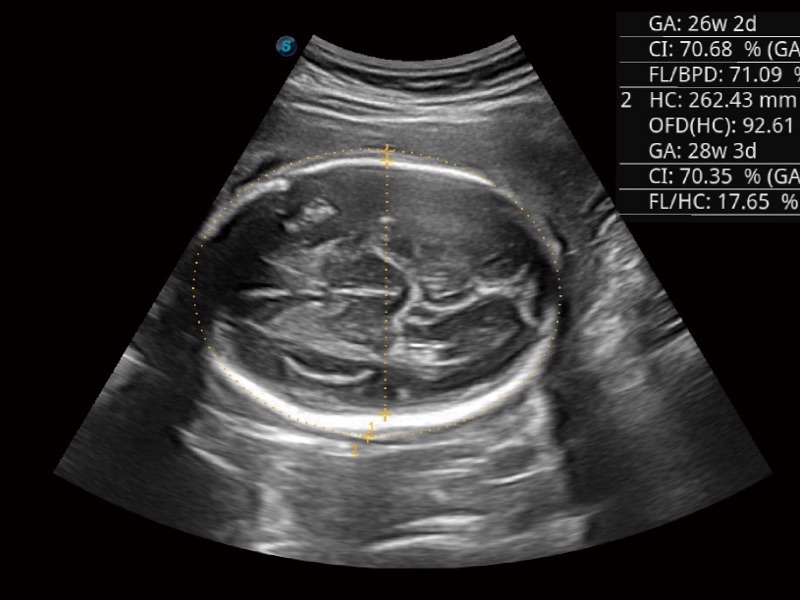

婦產(chǎn)科應(yīng)用

三維光影成像技術(shù)采用新型的渲染方式,增強(qiáng)邊緣信息,使得輪顯示清晰完整,為臨床提供豐富、直觀的三維結(jié)構(gòu),提供臨床診斷準(zhǔn)確性。